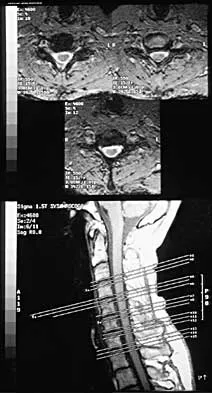

A 44-year-old woman has had lower extremity dysesthesias, urinary incontinence, and has been unable to walk for the past 2 days. She reports no pain or history of trauma. She notes that 3 weeks ago she missed work for 2 days because of back pain, but it resolved with rest. Examination shows decreased or absent sensation below the knees, no motor function below the knees, and decreased rectal tone. Catheterization results in a postvoid residual of 2,000 mL. Plain radiographs and MRI scans without contrast are shown in Figures 1a through 1d. What is the next most appropriate step in management?